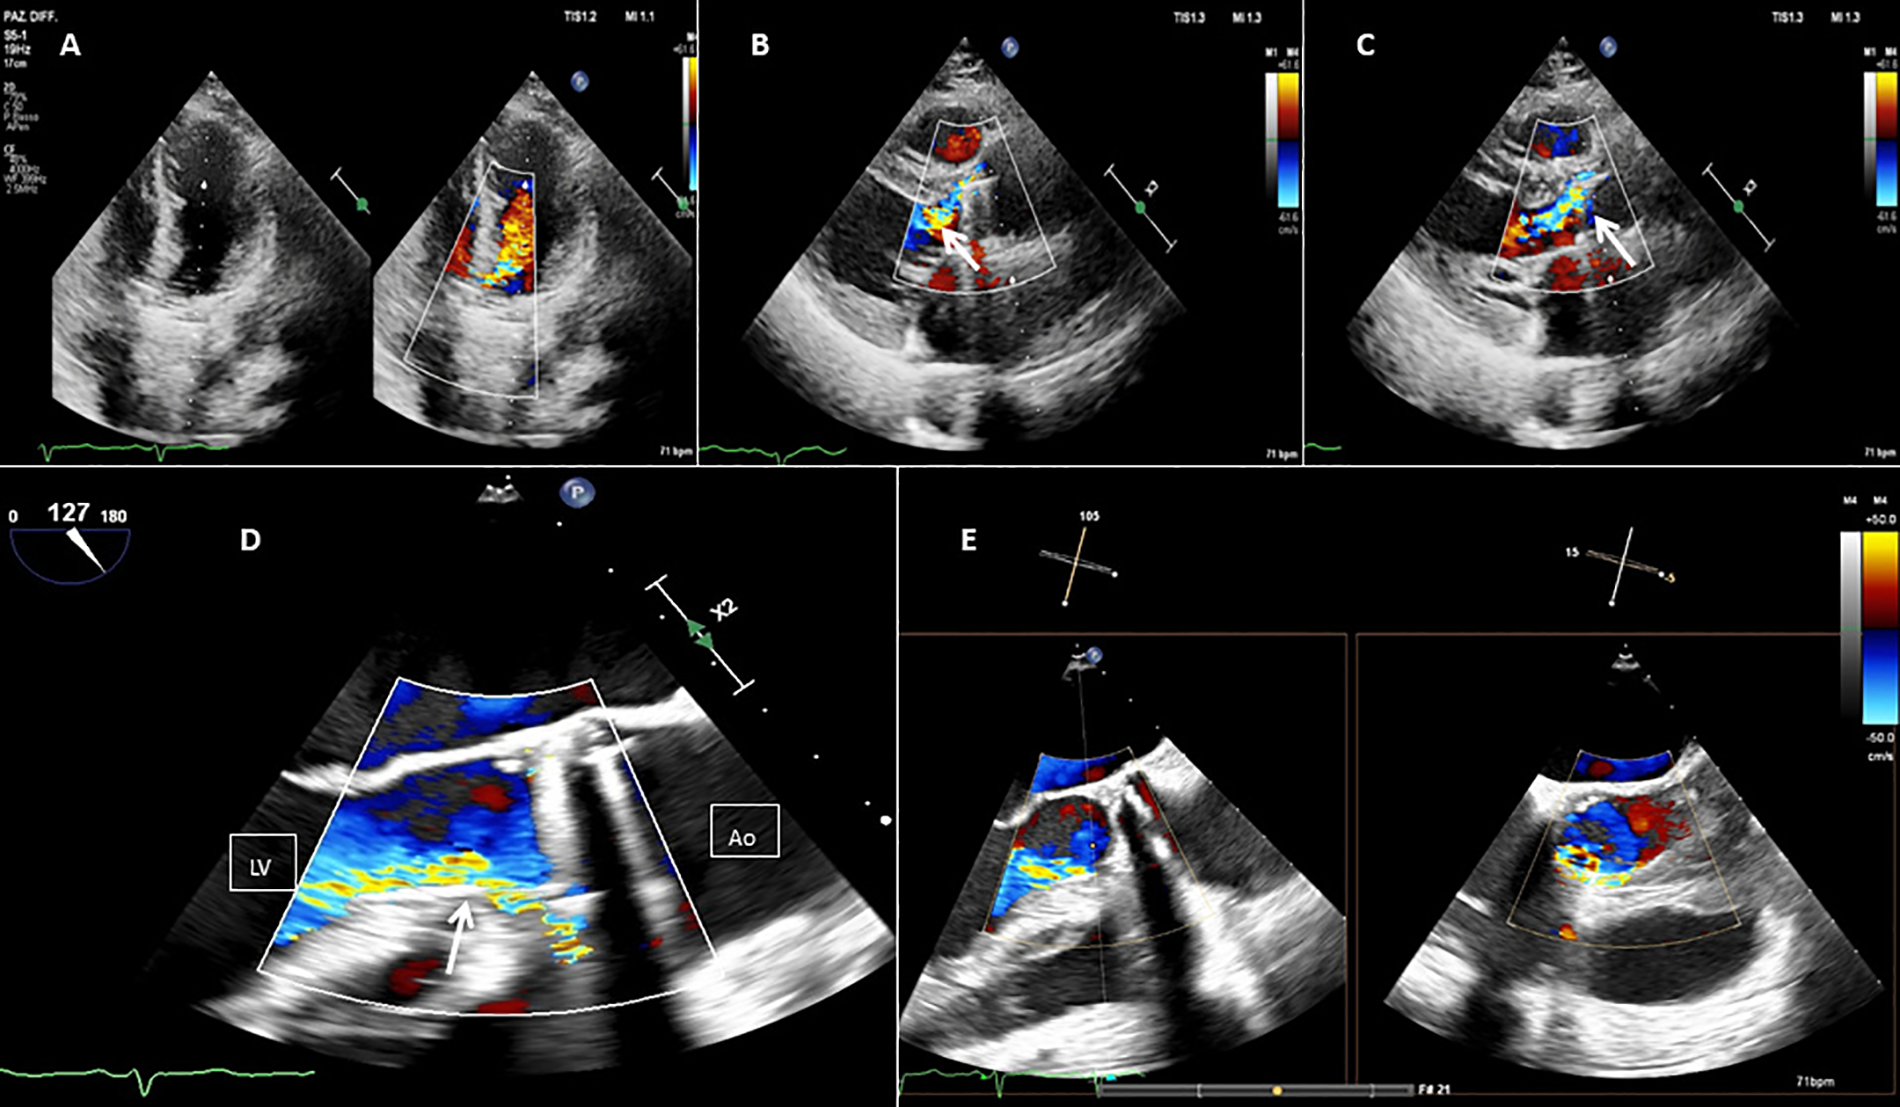

Subsequent imaging (2019–2021) showed mild residual PVL regurgitation with normal valve function. However, by 2024, two-dimensional transesophageal echocardiography (2D TEE) and multidetector computed tomography angiography (MDCTA) confirmed moderate-severe PVL regurgitation (vena contracta width 0.6 cm) near the right coronary cusp (Figures 1, 2). A coincidental DCRV was also identified (Figure 3, Supplementary Video 1). Given the prohibitive surgical risk, transcatheter PVL closure was planned.

Figure 1

Baseline 2D TEE color Doppler at the apical five chamber view (A), at the parasternal long axis view (B,C), at the mid-esophageal (ME) long axis view (D), and at the ME long axis view with Xplane (E), showing an On-X® prosthetic aortic valve with moderate-to-severe regurgitation (orange arrow) through a long paravalvular leakage. Red line, PVL; LV, left ventricle; Ao, aortic valve.